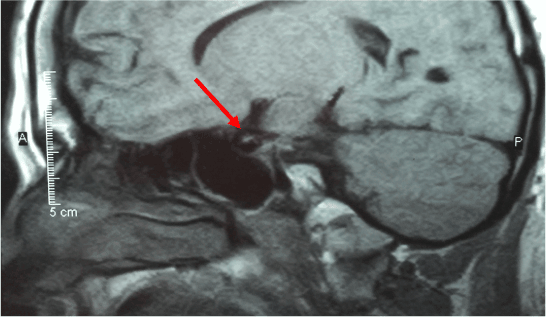

A 37 year old male, with a history of diabetes mellitus type 2, obesity, hypertension, hyperlipidemia, panhypopituitarism, and septo-optic dysplasia. He had been followed for a 16 year duration at yearly intervals. A CT of the brain revealed a small sella turcica, and a small infundibulum with hypoplasia of the pituitary gland. An MRI of the brain was also obtained, revealing decreased pituitary parenchyma within a small sella turcica. A soft tissue nodule in the hypothalamic region measuring approximately 8mm in diameter, was presumed to represent a regenerated or ectopic posterior pituitary. The corpus callosum and septum pellucidum were normal in appearance, however the optic chiasm was hypoplastic (Figure 1). The patient was also followed by neuro-endocrinology and neuro-ophthalmology at the University of California, San Francisco and endocrinology at the University of California, Davis. The patient was presumed to have no diabetic retinopathy by ophthalmology or neuro-ophthalmology, since the diagnosis. Previous attempts of fundus photography and optical coherence tomography were unsuccessful.

Figure 1: Sagittal view of an MRI of the brain.